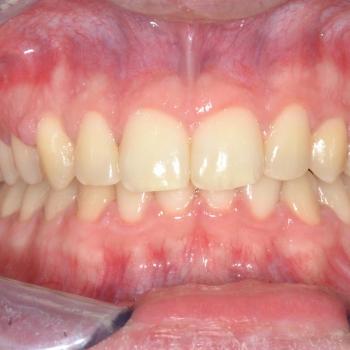

Ádám kitartásának köszönhetően a kezelés végére minden maradó fog a helyére került és egy esztétikailag és funkcionálisan is tökéletes harapást kaptunk.

A kezelés teljes időtartama: 3 év